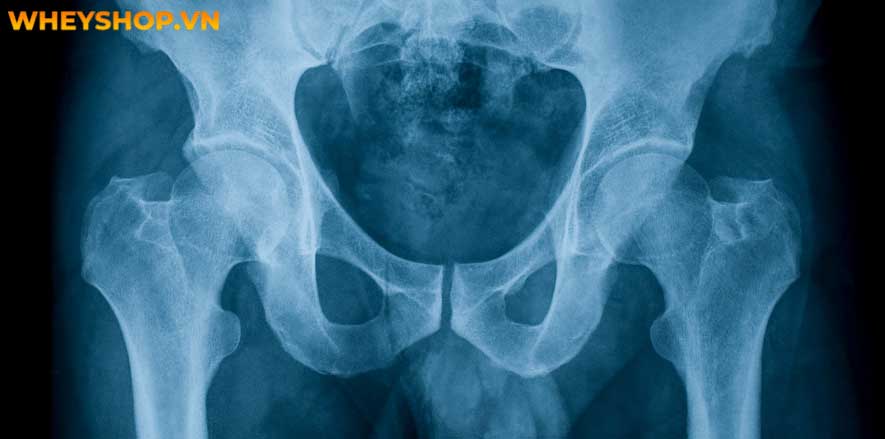

Ở phụ nữ, vùng xương chậu, bao gồm cả hậu môn, là bộ phận phải chịu đựng nhiều nhất khi đạp xe. Khi đạp xe và thực hiện các động tác mạnh, có nhiều ma sát với yên xe, bộ phận này có thể dễ dàng gây ra dị tật ở bộ phận sinh dục nữ. Trong trường hợp nghiêm trọng, nó có thể làm giảm ham muốn tình dục của phụ nữ và có thể dẫn đến vô sinh nếu xương chậu bị chèn ép quá nghiêm trọng.

Trên thực tế, hầu hết các tác hại của việc đi xe đạp đối với khả năng sinh sản đã được đề cập ở trên. Điều này là do việc đạp xe được thực hiện không chính xác hoặc quá sức. Bạn nên tham khảo bài tập đạp xe phù hợp và tần suất vừa phải để có sức khỏe dẻo dai và tốt nhất là không ảnh hưởng đến cơ thể.